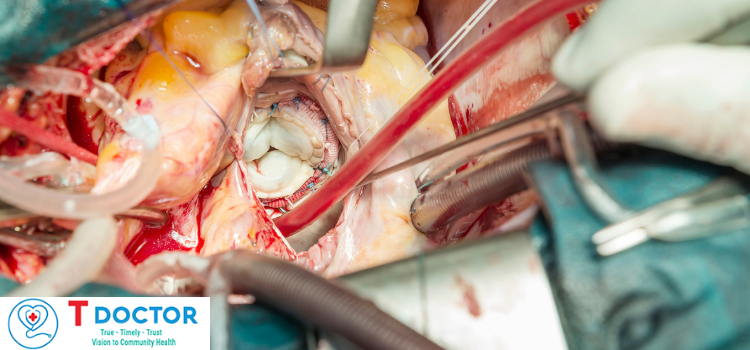

HỖ TRỢ BỆNH NHÂN TIM MẠCH

PGS.TS.BS.Hoàng Anh Tiến

Phó Giám đốc Trung tâm Tim mạch, Phó Trưởng Khoa Nội Tim mạch

BỆNH VIỆN TRƯỜNG ĐẠI HỌC Y DƯỢC HUẾ

HỖ TRỢ BỆNH NHÂN TIM MẠCH

PGS.TS.BS.Hoàng Anh Tiến

Phó Giám đốc Trung tâm Tim mạch, Phó Trưởng Khoa Nội Tim mạch

BỆNH VIỆN TRƯỜNG ĐẠI HỌC Y DƯỢC HUẾ